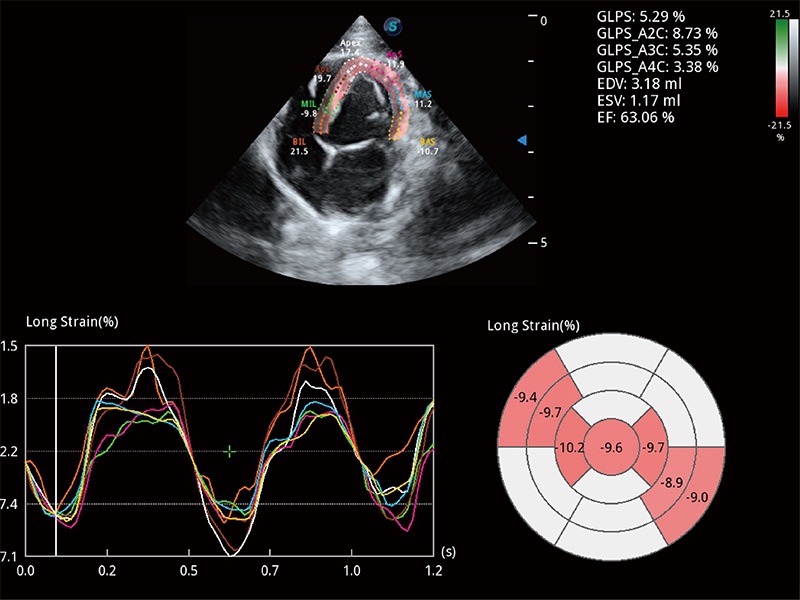

实时用颜色表示心肌组织运动,观察和定量组织的运动情況,对快速检测与评估心肌的灌注和活性、电传导及心肌收缩和舒张功能等均能提供重要的诊断信息。

通过心肌识别技术与二维斑点追踪技术相结合,对心脏的超声图像进行量化分析。计算心肌17个节段的应变、应变率、速度、位移等,并通过牛眼图的形式进行呈现。

通过360度任意调节3条M型取样线,在同一心动周期上观察心脏不同位置的运动曲线,得到准确的心功能测量数据,有效评估心肌运动及左心室功能。

具备多种协议可选,同时支持17阶段划分法和专业的SE报告。

能够基于左心室壁追踪和辛普森法,自动计算射血分数,支持多个可移动点描迹,与手动测量相比,极大节省了动物医生的时间和精力。